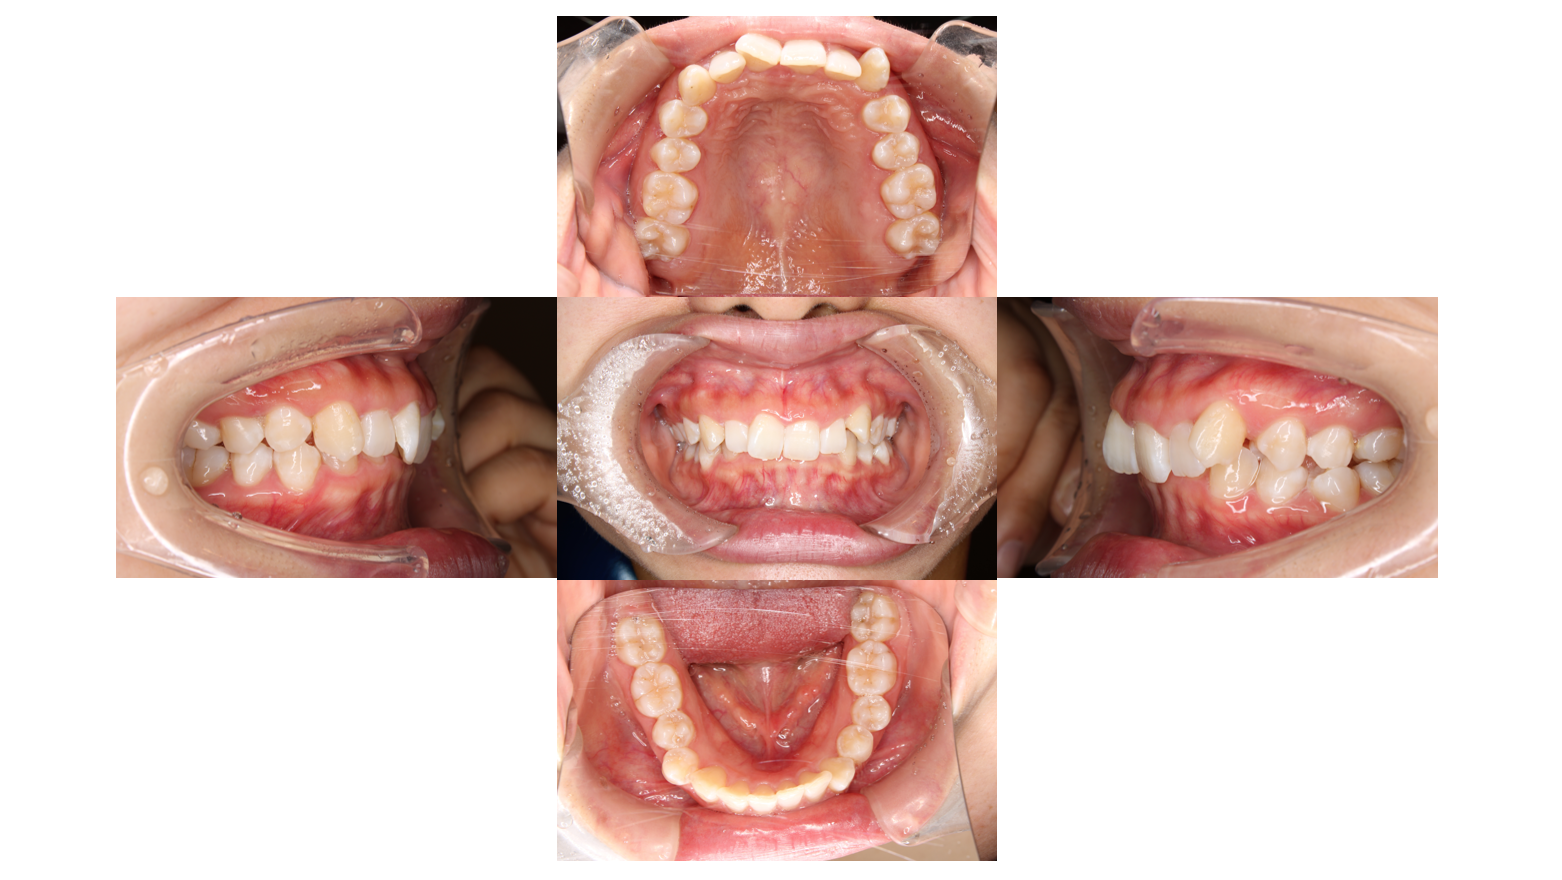

Before

年齢層 | 20代 |

---|---|

性別 | 女性 |

主訴 | 【主訴】かみ合わせが深い【診断・症状】過蓋咬合 |

治療費用 | 検査・診断:税込38,500円/裏側矯正治療(リンガル矯正):税込1,397,000円 |

治療期間 | 1年4か月(17回) |

抜歯 | 無(非抜歯) |

矯正の装置 | リンガル矯正 |

副作用・リスク | 歯肉退縮,歯根吸収,疼痛,咬合の違和感,装置の違和感,虫歯,歯肉炎 |

初診